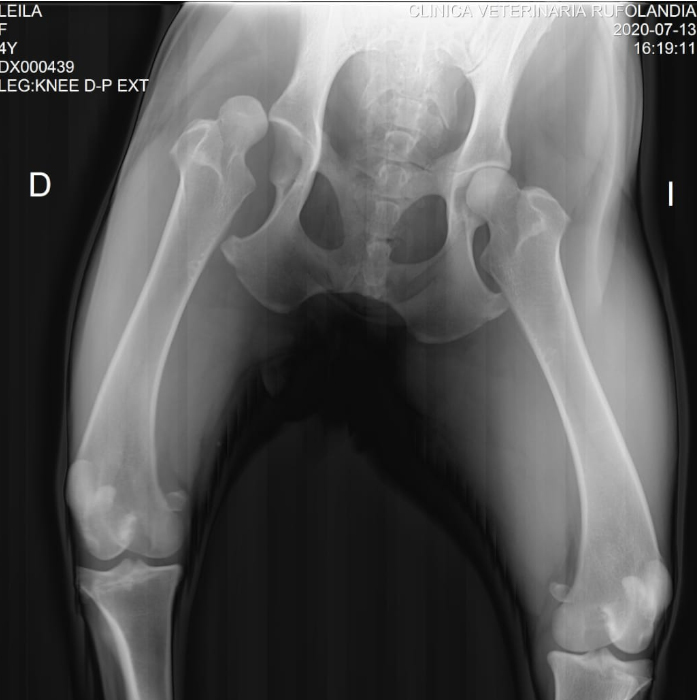

Guadalupe es una tierna y juguetona perrita que vivia en una finca. Desafortunadamente en medio de uno de sus juegos se LUXO su cadera.

La intentamos ayudar con una primera cirugia pero como llevaba tanto tiempo con esta Luxación no fue posible que saliera adelante...

Por el estado de mi femur, tenemos dos opciones para la cirugia: Una es cortar la cabeza de mi femur, pero a largo plazo es contraproducente para mi otro femur.

La segunda opción es un reemplazo de cadera, que me dara una mejor calidad de vida pero es mas costosa, y por esto estamos realizando estas rifas